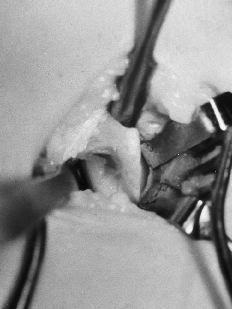

Mediante un acceso medial se alcanzó a la zona por el lado posteromedial del músculo bíceps. Se pudo observar la presencia de una prominencia ósea con un refuerzo fibroso que se dirigía desde la punta de la misma hacia la epitróclea, correspondiendo al denominado ligamento de Struthers (Fig. 2); algunas fibras musculares del pronador redondo se insertaban en la zona más distal de la apófisis. Tras la exposición de la apófisis se apreció su forma de gancho, con una base amplia y de unos 2 cm de longitud, situada en la cara anteromedial del húmero, que se dirigía hacia abajo, adelante y medialmente. En contacto con su cara interna (cubital) se distinguía el nervio mediano y, más medialmente, la arteria humeral, sin que ninguna de estas estructuras presentara alteraciones. No se evidenció ninguna estructura neurovascular en la zona lateral (radial) de la apófisis. Tras la disección anatómica, nerviosa y vascular se procedió a la resección de la exóstosis mediante escoplo, tallando un cajeado de la base de implantación en el húmero (Fig. 3). El período postoperatorio transcurrió sin alteraciones y a los 12 días se retiró el vendaje y los puntos. En la revisión a los 6 meses la paciente estaba asintomática y sin evidenciar signos de recidiva en la radiografía.

Figura 3. Imagen quirúrgica. Se observa la ausencia de estructuras neurovasculares anterolaterales a la apófisis.

Su base es amplia y se localiza en la cara medial del húmero, a unos 5-7 cm de la epitróclea, con dirección caudal, anterior y medial,14,21 sin sobrepasar los 2 cm de longitud.14,21 En algunos casos como ocurre en el de este trabajo aparece una formación fibrosa que se dirige desde la punta de la apófisis hasta la epitróclea, conocida como ligamento de Struthers, banda supracondilar o bandeleta supraepitrocleana. Laha y cols.14 han descrito cuatro tipos en la forma de esta variante ósea dependiendo de su tamaño y de la aparición y estructura del ligamento: la forma más simple es una prominencia, que no suele producir signos clínicos; la segunda es la apófisis propiamente dicha, que puede tener expresión clínica; el tercer tipo, que correspondería al caso presentado, es la apófisis con ligamento, y por último, el cuarto tipo es la calcificación del ligamento, que formaría un foramen óseo desde la base de implantación de la apófisis hasta la epitróclea. Este último es el orificio o anillo supraepitroclear. Se ha descrito la presencia de una inserción anómala del pronador redondo,1,10,11,14 como ocurre en nuestro caso (Fig. 4), y más raramente de los músculos braquial15 y coracobraquial.1,14 Algunos autores consideran que estas inserciones anómalas pueden ser más responsables de los signos y síntomas que la propia presencia de la apófisis supraepitroclear.4 Así, la contracción del pronador redondo comprimiría el nervio mediano contra el canal y sería éste músculo la causa de la irritación nerviosa.1